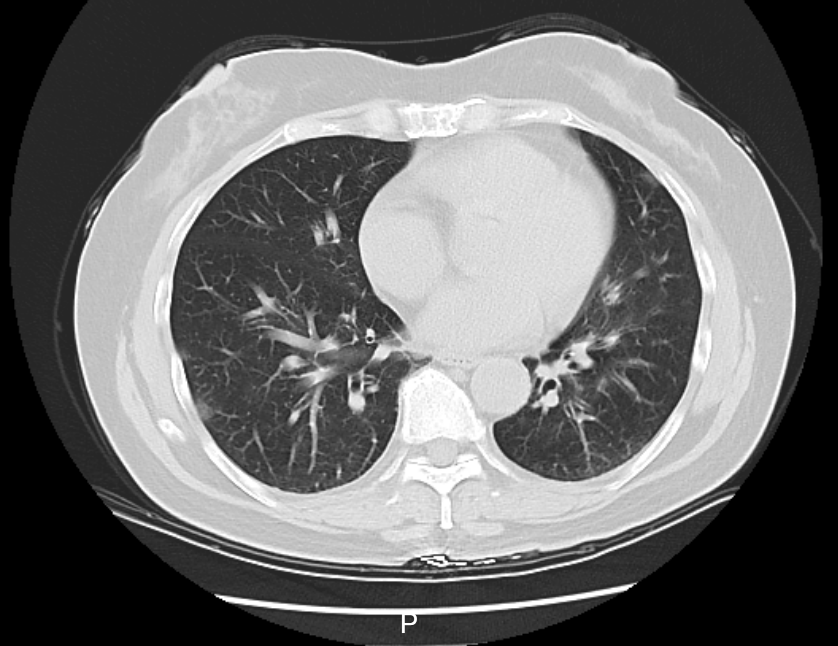

“Chúng tôi mới đi du lịch một tuần trước. Sau khi trở về, tôi bắt đầu xuất hiện các triệu chứng sốt, ho, đau họng và đau nhức cơ thể. Tôi đã chịu đựng triệu chứng này trong vài ngày nhưng đến hôm kia, do không thể tiếp tục chịu đựng nên tôi đã nhanh chóng đến bệnh viện địa phương để chụp X-quang lồng ngực. Các bác sĩ cho biết tôi bị biến chứng viêm phổi và khuyên nên nhập viện ngay” - Cô Lý (50 tuổi, đã thay đổi tên) lấy tờ báo cáo chụp X-quang có dòng chữ “viêm phổi góc dưới bên trái” với các vết trắng phổi cho hay.

Kết quả xét nghiệm cho thấy, cô Lý cùng gia đình đều dương tính với virus cúm A và riêng cô Lý đã biến chứng viêm phổi. Sau 2 ngày điều trị, thân nhiệt của cô Lý đã trở lại bình thường và các triệu chứng như ho, đau họng cũng cải thiện đáng kể.